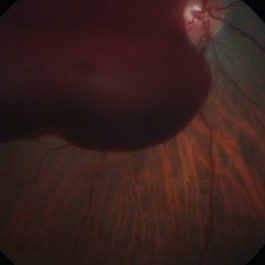

Rerinal Detachment with PVR

Sep 10 2014 by Mehul A Shah

A myopic male patient 35-years-old presented to outdoor and found to have retinal detachment with multiple fixed folds.

Photographer: Drashti Netralaya,Dahod

Imaging device: FF 450

Condition/keywords: proliferative vitreoretinopathy (PVR)